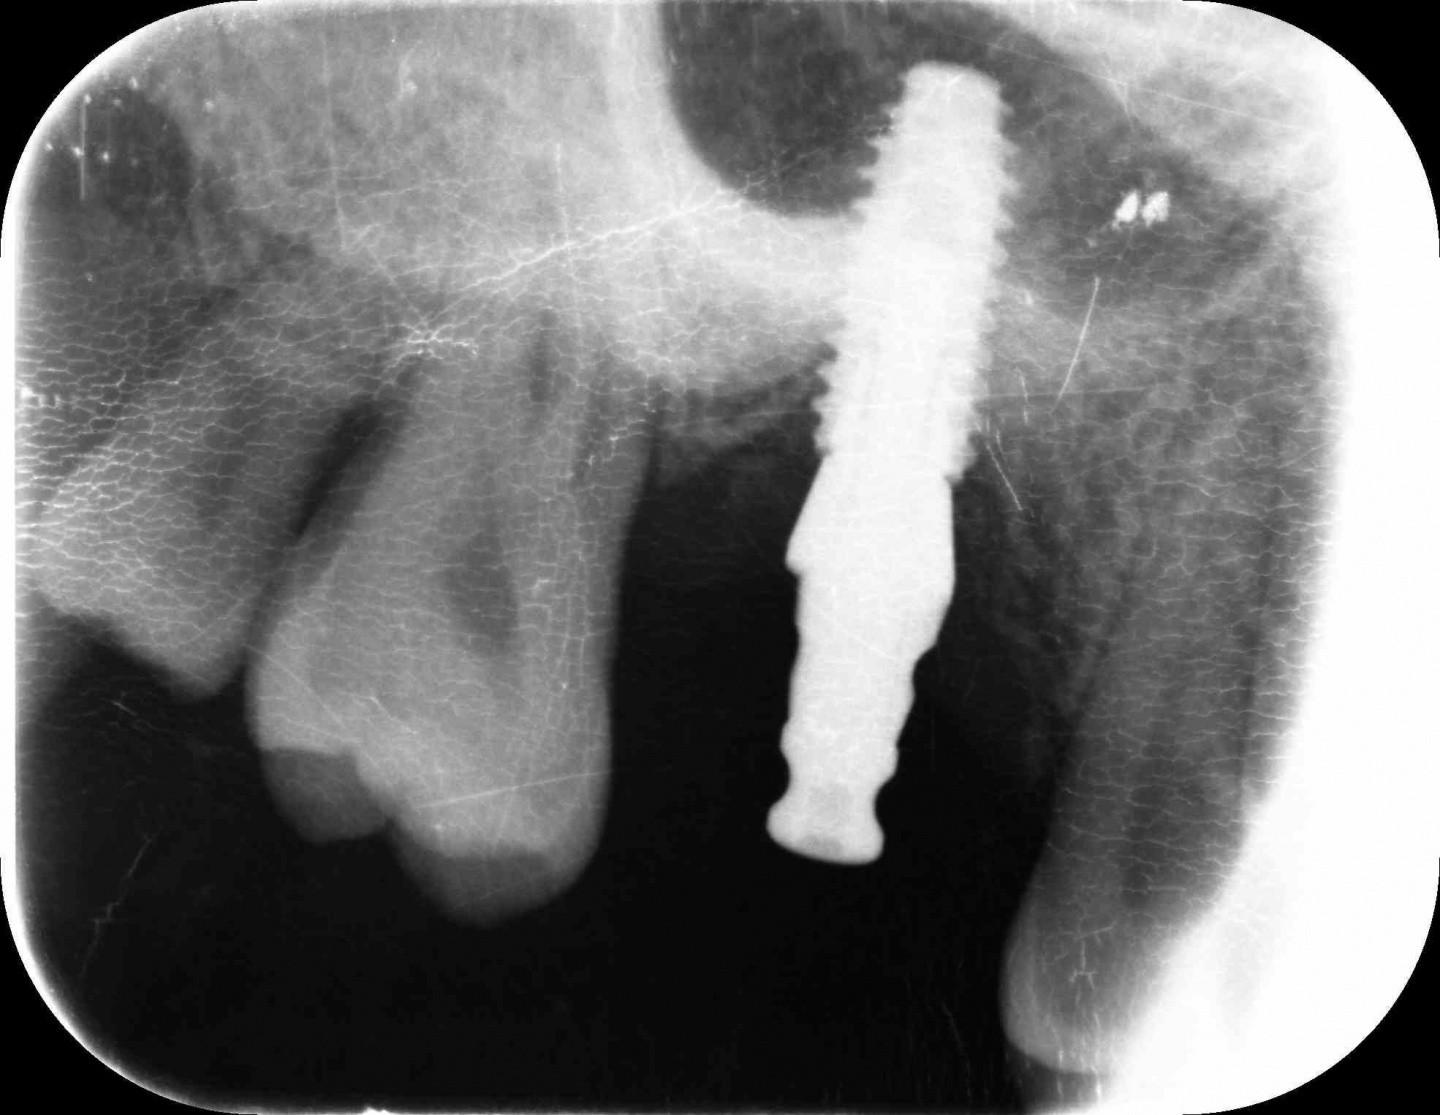

| 0114 #16 右上第一大臼齒 |

![]() |